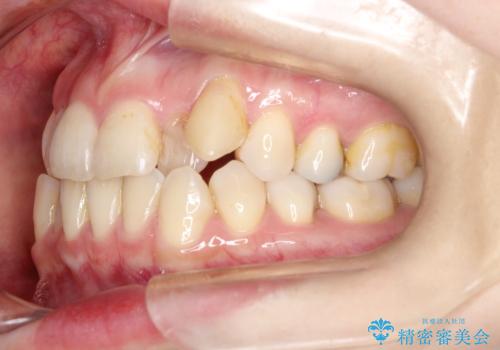

初診時の歯並びの状態としては、上下ともに前歯部中心としたの中等度のがたつき(叢生)があり、全特に左上の前歯は1本だけ引っ込んでおり、犬歯は外に飛び出した状態でした。